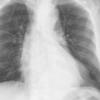

Ao Diss 1b

Date: 01/21/2006

Views: 3003